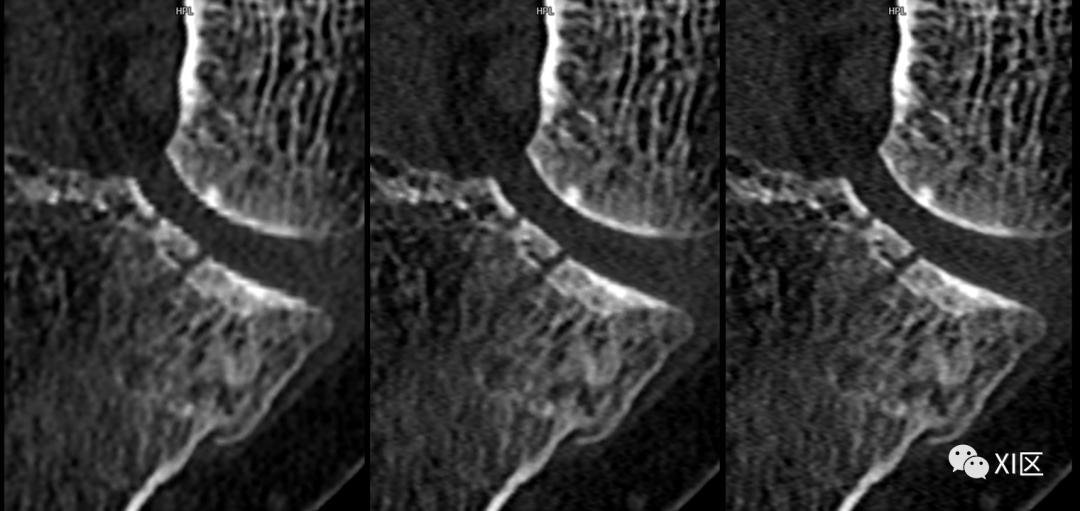

SOMATOM Definition Flash光子CT常规重建0.6 mm(128x0.6 mm)图像(左)与IVR重建0.6 mm(384x0.6 mm)图像(右)比较。使用IVR技术的图像关节面更平滑,骨小梁及骨折细节显示更清晰。

SOMATOM Force CT常规重建0.6 mm(192x0.6 mm)图像(左)与IVR重建0.6 mm(288x0.6 mm)图像(中)0.6 mm(576x0.6 mm)比较(上排:全局视图;下排:局部放大显示)。使用IVR技术的图像关节面更平滑,骨小梁及骨折细节显示更清晰。